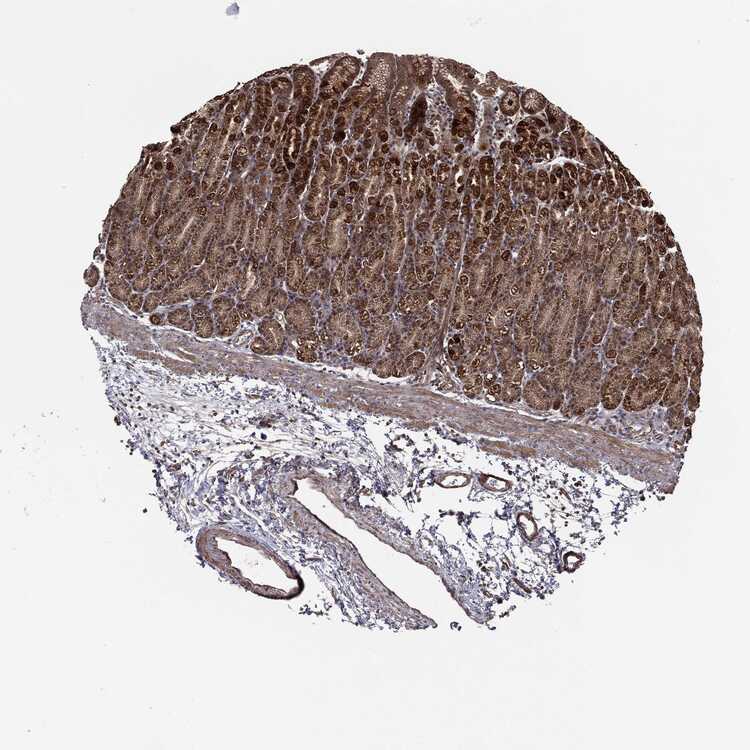

TISSUE PRIMARY DATA STOMACH Show tissue menu

STOMACH 1 - Antibody stainingi

Antibody staining in the annotated cell types in the current human tissue is reported as not detected, low, medium, or high, based on conventional immunohistochemistry profiling in selected tissues. This score is based on the combination of the staining intensity and fraction of stained cells.

Each image is clickable and will lead to virtual microscopy that enables deeper exploration of all samples and also displays staining intensity scores, fraction scores and subcellular localization as well as patient and tissue information for each sample.

Antibody CAB069425Antibody CAB080053Antibody CAB080065Antibody CAB080070Antibody CAB080081Antibody CAB080095Antibody CAB080097

Glandular cells HighHighMediumMediumNot detectedHighHigh